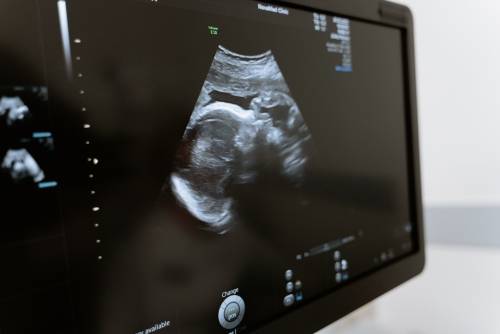

常规超声检查指的是二维超声检查,二维超声检查即二维超声检查,小排畸是为了更好地观察胎儿生长发育情况,排除畸形的检查。小排畸检查能够排除绝大多数胎儿畸形,如先天性心脏病、唇腭裂、水肿胎,以及多指畸形、重度脑膨出等。

1、先天性心脏病:可通过二维超声检查直接观察心脏及大血管的形态、结构、连续性及血流改变,二维超声检查比较直观,能够显示出心脏的三维图像,所以在怀孕期间需要定期做产检,一般在怀孕20-26周需要做四维彩超大排畸检查,判断胎儿是否有畸形;

2、唇腭裂:二维超声检查能够比较清晰地显示出胎儿嘴唇及面部发育情况,而且还能够观察到是否存在唇腭裂的情况,所以在怀孕期间需要常规做三维彩超检查,判断胎儿是否存在唇腭裂;

3、水肿胎:如果孕妇出现水肿胎,也需要做二维超声检查,判断胎儿是否存在水肿胎,因为如果孕妇出现水肿胎,大多是由于妊娠期高血压导致,所以在怀孕期间要定期做产检,随时观察水肿胎的情况;

4、多指畸形:产前二维超声检查可以观察到胎儿手指、脚趾等外观畸形,如果出现多指畸形,还需要做三维超声检查,判断是否有多指畸形的情况;

5、重度脑膨出:二维超声检查能够比较清晰地观察胎儿脑组织、脊柱、羊水等情况,如果出现重度脑膨出,也需要做三维超声检查判断是否有脑积水。

孕期需要做好定期产检,建议在怀孕24-26周需要到医院做四维彩超大排畸检查,判断胎儿是否有畸形,如果出现比较严重的畸形,建议在医生指导下终止妊娠。